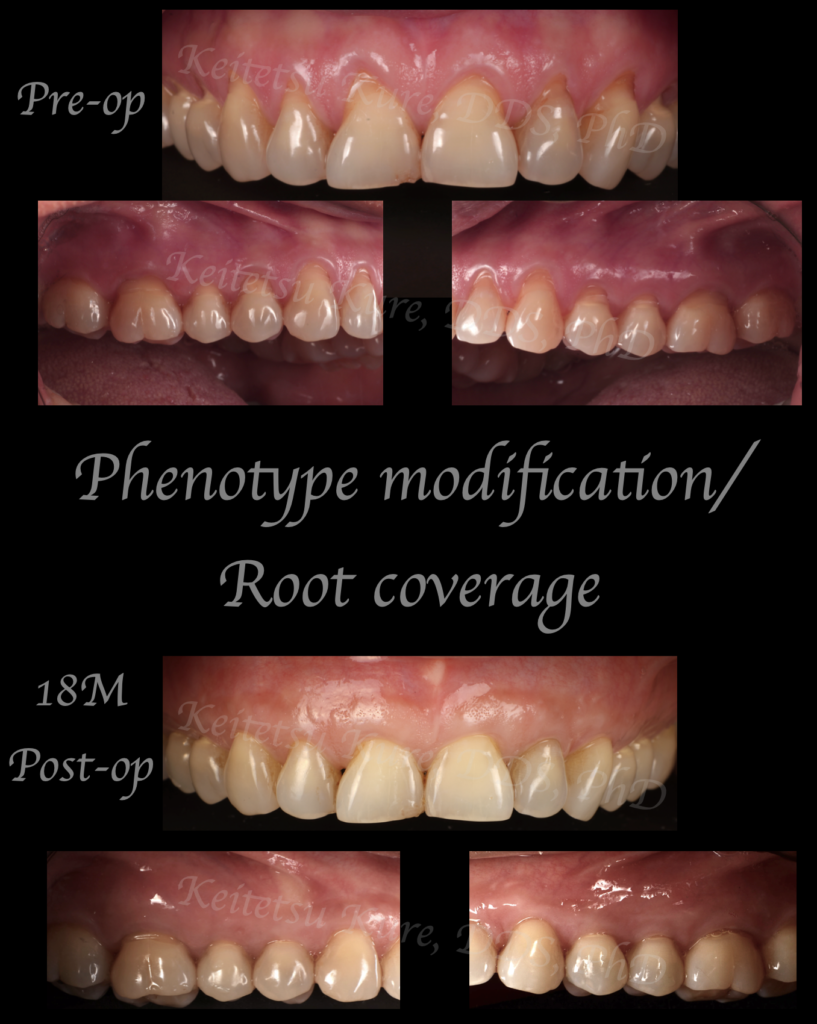

今回の患者さんは、全顎的な歯肉退縮と重度の知覚過敏症に悩まされ、これまでに考えられるあらゆる非外科的治療を行っても改善が得られなかったため来院されました。(重要なのは知覚過敏症を改善するためにまず非外科・非侵襲的なアプローチを検討し、頼みの綱として外科処置を検討すべきです。)そこで本症例では、口蓋から自家結合組織を採取し、全歯同時の根面被覆/PMTの治療を行いました。治療から1年半が経過した現在も、歯肉退縮の明らかな改善、歯肉の厚みの増加が安定して認められています。

歯肉の厚みを増加させることは、単なる審美的改善にとどまらず、将来的な歯肉退縮の進行を予防し、長期的な組織安定性を確保するうえで極めて重要です。本症例は、根面被覆だけでなくPMTを併用することの意義を示す一例と考えられます。